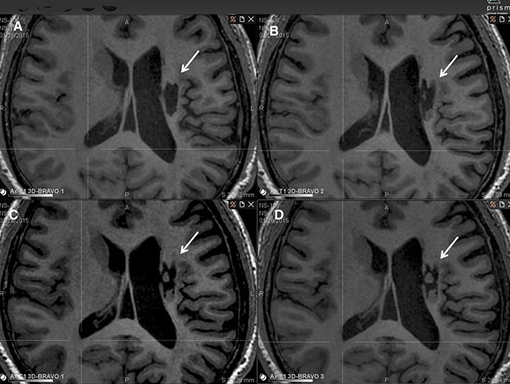

影像學(xué)檢查:在 6 個月的隨訪中,所有 9 名受試者均觀察到新組織,源自腦軟化梗塞腔。該腔內(nèi)組織外觀具有以下特征:短期活力(術(shù)后第一次 MRI 與基線相比的組織外觀)—9 例中有 9 例;生長(術(shù)后至少兩次 MRI 中新組織增加)—6 例中有 6 例;穩(wěn)定(術(shù)后至少兩次 MRI 中新組織沒有變化;即生長平臺期,最長為 24 個月)—6 例中有 5 例;無法獲得 24 個月后的長期活力。

(A)基線時,(B) 6 個月隨訪時,(C) 12 個月隨訪時,(D) 24 個月隨訪時。